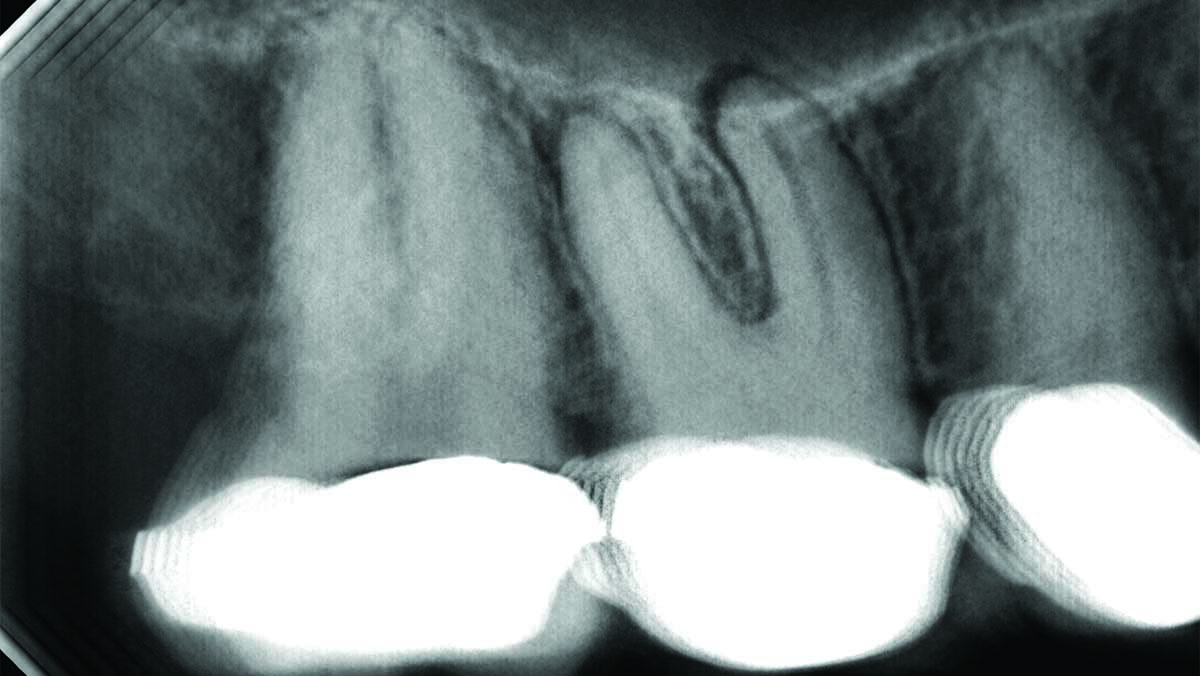

Deep Shape in Endodontics: Significance, Rationale and Benefit

The goal of endodontic treatment is to prevent or cure, when present, Lesions of Endodontic Origin, at times referred to as apical periodontitis. The role of bacteria in the pathogenesis of endodontic disease is well established, and therefore, it is critical to eradicate these pathogens by employing the highest level of presently developed standards. This … Read more